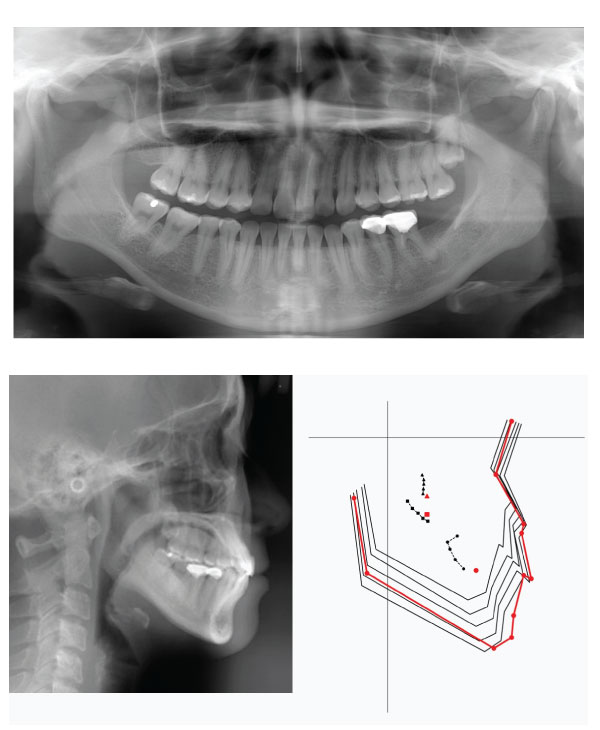

The space analysis showed 8.0 mm of space deficiency in the upper dentition and 1.5 mm space deficiency in the lower dentition. Both upper and lower dental arches were symmetric ovoid shape (Figure 1). Panoramic findings showed #13 missing and #27 elongation (Figure 2). Cephalometric analysis indicated that this patient had a skeletal Class I pattern with an ANB angle of 3.4 ° with a mean mandibular angle. The upper incisor positions showed tendency of mild retroclination measured from U-1 to A-P plane of 5.3mm. The mandibular incisors were retroclined as compared to norms. (Figure 3, Table 1).

Figure 3: Initial Cephalometric radiograph

Figure 5: Post-treatment Panoramic and Cephalometric radiograph

Figure 6: Cephalometric superimposition of initial (Black line) and post-treatment(Red line)